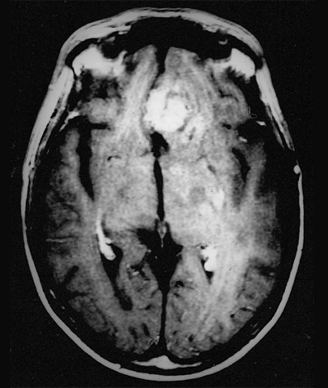

Recurrent glioblastoma multiforme

In mouse models, the CAR T cells could control the growth of tumors expressing human EGFRvIII, as measured by magnetic resonance imaging scans of the mouse brains. In some mice, the tumors disappeared entirely.